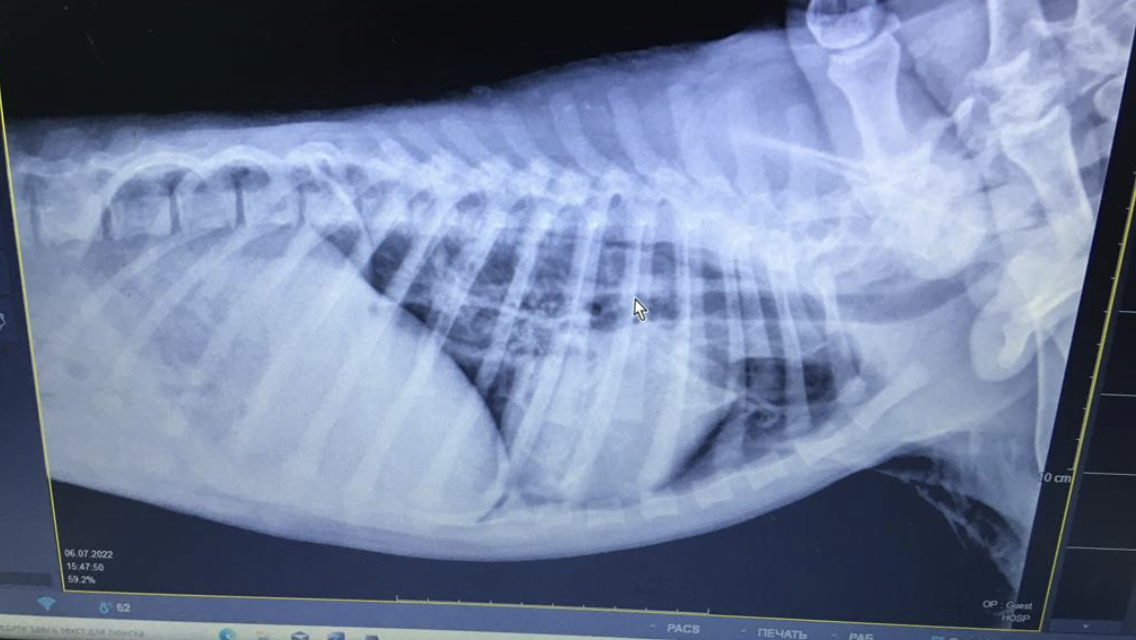

Сейчас оба щенка выздоравливают, оба на передержке, за ними очень хороший уход. Мальта регулярно наблюдается у врача.

Последний осмотр и рентген показали, что рёбра срослись и девочку ничего не беспокоит. Вот её все выписки с диагнозом и рентгеном